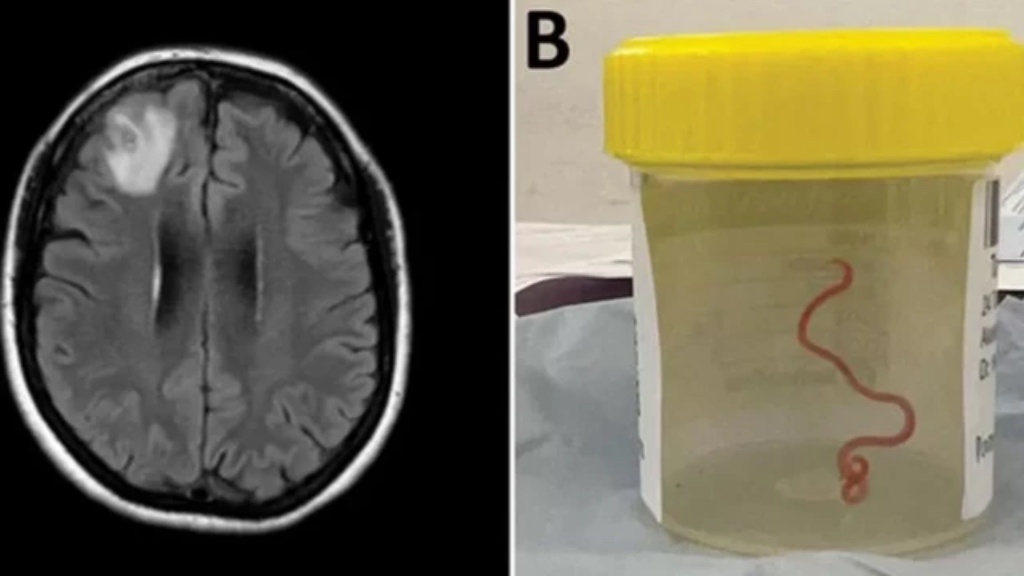

Это «малыша» нашли в мозге несчастной женщины…

Через год (!) у женщины появились признаки депрессии и эпизоды забывчивости. МРТ показало поражение в правой лобной доле головного мозга. Тут уже в больнице решились на довольно сложную процедуру: биопсию мозга. И вот тут наконец была найдена причина симптомов.

Проведя биопсию, врачи с удивлением обнаружили в мозге... живого паразита. Червь был около 8 см в длину и 1 мм в ширину. И это был гельминт. Глист в простонародье. В мозге!

Паразита извлекли, окружающие ткани исследовали — других гельминтов не обнаружили. После операции женщине назначили сложную комбинацию противопаразитарных препаратов, чтобы уничтожить всех, кто решил в ней поселиться. В течение шести месяцев симптомы полностью исчезли.